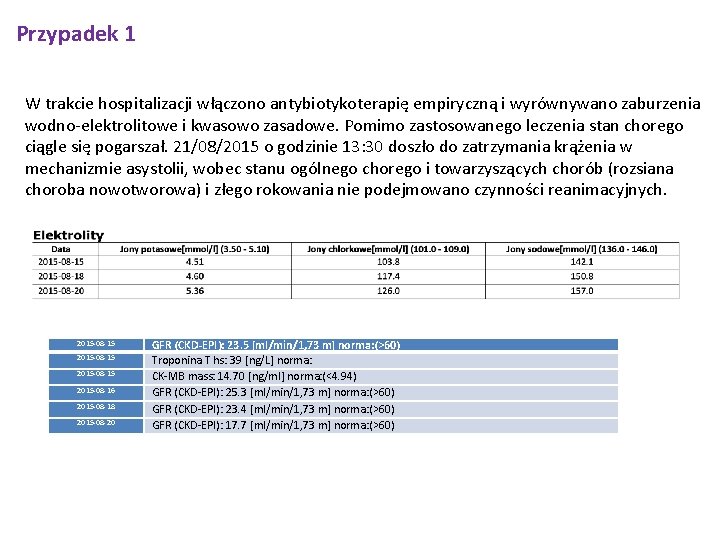

Przypadek 1 W trakcie hospitalizacji włączono antybiotykoterapię empiryczną i wyrównywano zaburzenia wodno-elektrolitowe i kwasowo zasadowe. Pomimo zastosowanego leczenia stan chorego ciągle się pogarszał. 21/08/2015 o godzinie 13: 30 doszło do zatrzymania krążenia w mechanizmie asystolii, wobec stanu ogólnego chorego i towarzyszących chorób (rozsiana choroba nowotworowa) i złego rokowania nie podejmowano czynności reanimacyjnych. 2015 -08 -15 2015 -08 -16 2015 -08 -18 2015 -08 -20 GFR (CKD-EPI): 23. 5 [ml/min/1, 73 m] norma: (>60) Troponina T hs: 39 [ng/L] norma: CK-MB mass: 14. 70 [ng/ml] norma: (<4. 94) GFR (CKD-EPI): 25. 3 [ml/min/1, 73 m] norma: (>60) GFR (CKD-EPI): 23. 4 [ml/min/1, 73 m] norma: (>60) GFR (CKD-EPI): 17. 7 [ml/min/1, 73 m] norma: (>60)